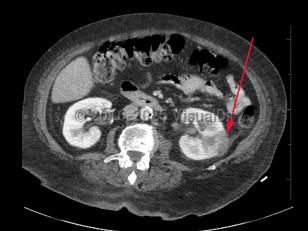

Pyelonephritis

Patients present with a triad of flank pain, fever, and nausea / vomiting. There are often associated symptoms including dysuria, urinary urgency, or urinary frequency. The patient can also have concurrent noninfectious complicating conditions like renal calculi and renal infarction. Gross hematuria may occasionally be seen. Patients with spinal cord injury or dementia may present atypically, but fever is expected to be present in cases of pyelonephritis. Examination may reveal costovertebral angle tenderness.

Complications of pyelonephritis include progression to sepsis and septic shock and, in rare cases, papillary necrosis, renal abscess, and perinephric abscess.